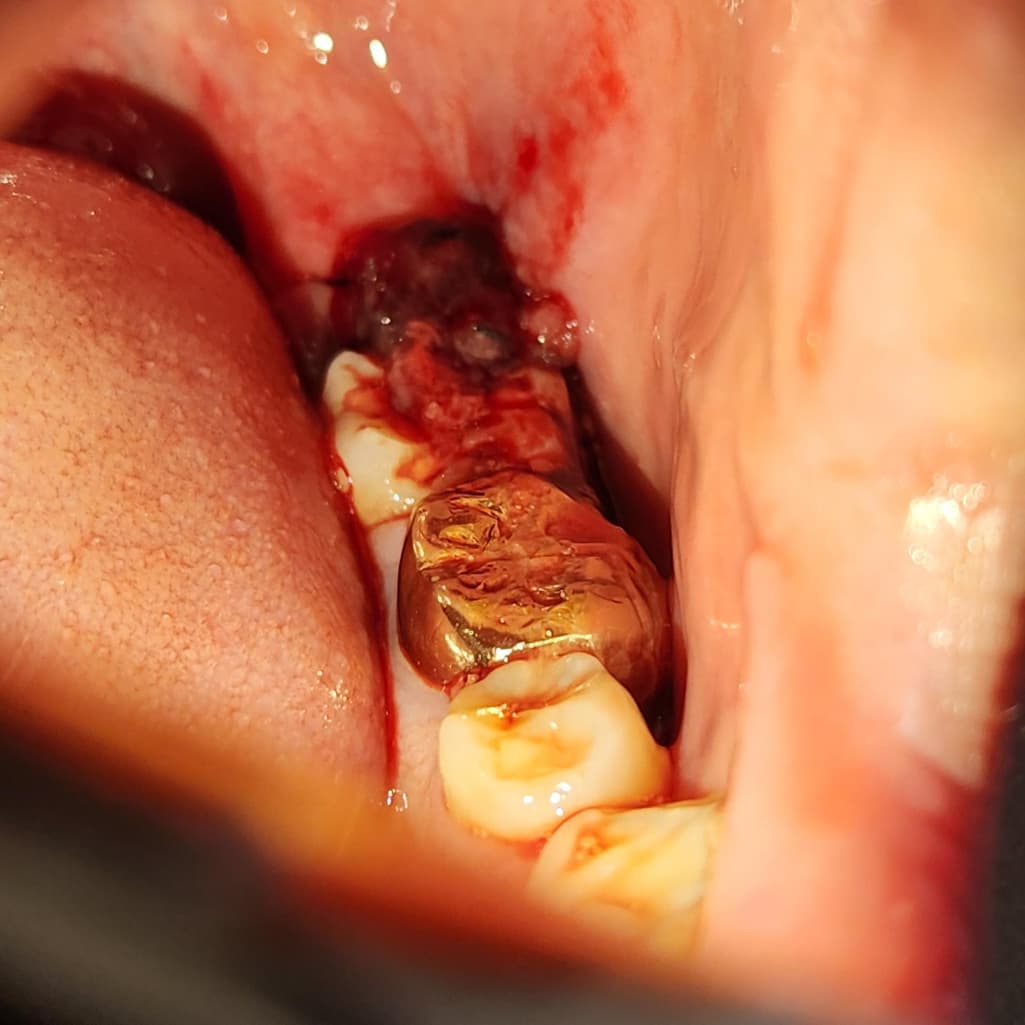

어제 오후2시에 사랑니를 발치 후 오후7시까지 출혈이 안멈춰서 거즈를 2시간마다 바꾸면서 잤습니다. 근데 오늘 새벽5시에 확인했더니 입 안에 피가 많이 고여있어서 가글을 하고 다시 2시간동안 거즈를 물었습니다. 그랬더니 어느정도 진정된거 같은데 사진을 보시다시피 괜찮은건가요?

그리고 사진 속 맨 끝에 피덩어리로 가려진게 실밥이고, 안보이지만 지렁이 모양으로 피덩어리가 옆에 있습니다. 이것도 원인인가요?

자극이 될 수 있으므로 과도한 가글은 삼가시고요 바깥으로 삐져나온 혈병(피떡)은 어차피 치유에 큰 의미가 없으니 걷어내셔도 됩니다. 지금으로서는 출혈이 있는 것은 아닌 것 같습니다.

저정도 출혈 상태라면 지혈이 된게 아니니 거즈를 더 꽉 물고 계셔서 지혈을 시켜주시는게 좋을것같습니다.